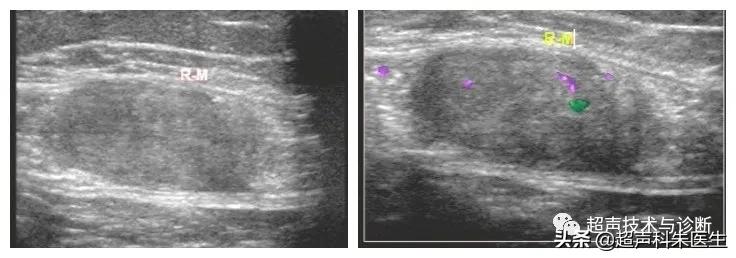

高频探头显示包块内部回声细节

超声所见:下腹部腹膜外探及一低回声团块,大小12.4*6.9*9.0cm,边界清楚,内部回声不均质,内见散在点状强回声及小片状无回声区,包块与腹直肌分界不清,CDFI观察:其内可见少量血流信号。